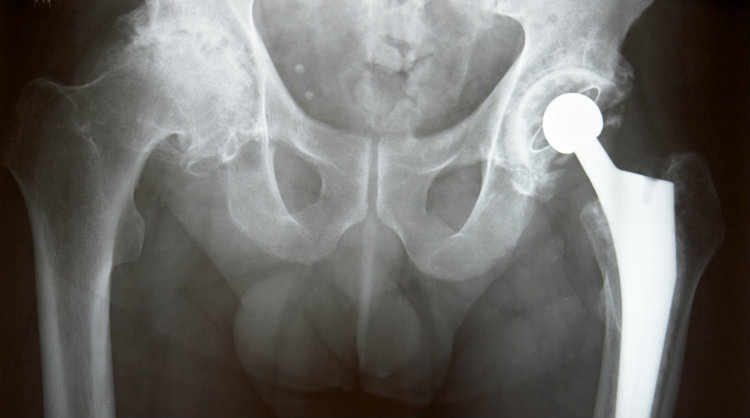

June 14, 2022, a motion was filed to consolidate all Exactech joint replacement lawsuits involving recalled polyethylene inserts in hips, knees, and ankles into a federal multidistrict litigation (MDL) in the Eastern District of New York. If the motion is granted, all future Exactech recall lawsuits filed in federal court would be centralized under the MDL.

In 2015, Gary Kline took Zimmer to court over its Durom Cup metal-on-metal hip implant. The jury found Zimmer liable for his health issues; however, the damages awarded were overturned on appeal. The trial court, in a decision upheld on appeal in 2018, ordered a new trial leading to a damages-only retrial.

The jury, asked to rule strictly on damages, unanimously awarded $7.68 million to Kline: $80,460.19 in past economic losses; $3.6M in past non-economic losses; and $4M in future non-economic losses.

On April 17, 2019, another lawsuit against Zimmer Biomet Holdings, Inc. was filed in the Superior Court of California for the County of Los Angeles. The lawsuit, Langford v. Biomet Inc., is one of many lawsuits in both state and federal courts the company is facing regarding heavy metal poisoning from its metal-on-metal hip replacements.

August 28, 2018. More lawsuits have been filed against Zimmer Biomet on behalf of patients who had to undergo a traumatic second revision surgery to remove the Biomet Magnum metal-on-metal hip implants.

May 3, 2018. Three more lawsuits have been filed against Biomet Orthopedics on behalf of patients who had to undergo traumatic hip revision surgery due to defective Biomet Magnum hip implants.